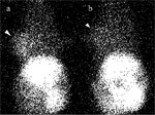

99mTc-HL91(99mTc 4,9-diaza-3,3,10,10-tetramethyldodecan-2,1-dione dioxime) hypoxic imaging was performed in 10 mice bearing sarcoma 180 (S180) before and after 2 h carbogen breathing. Radioactivity ratios of tumor to contralateral limbs (T/L) of the 2 images were calculated and compared. Mice bearing S180 were subjected to long-term carbogen breathing (2 h/day for 24 days), and were treated with or without 32P-colloid. Tumor growth rate was observed in the S180-bearing mice.

T/L of 99mTc-HL91 uptake before and after carbogen breathing was 1.872+/-0.391 and 1.354+/-0.189, respectively (t=4.476, P<0.01). In mice in the 32P-treated air breathing group and 32P-treated carbogen breathing group, tumor growth rate did not differ on day 12 after 32P-colloid treatment, and on day 24 the tumor volume was 2.728+/-0.469 and 2.237+/-0.603 cm3 (t=2.128, P<0.05), respectively, with tumor mass being 2.437+/-0.447 and 1.965+/-0.538 g (t=2.134, P<0.05), respectively. Conclusions: Long-term carbogen breathing can increase tumor oxygenation and continual carbogen breathing is necessary for enhancing the therapeutic effect of 32P-colloid interstitial irradiation.